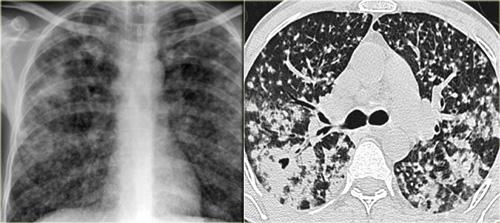

Đây là một trường hợp sarcoidosis phế nang.

Hình ảnh trông giống như tăng tỷ trọng dạng kính mờ, nhưng khi quan sát kỹ hơn có thể nhận thấy rằng sự tăng tỷ trọng này là kết quả của nhiều nốt nhỏ tập hợp lại.

Cũng lưu ý hạch to rốn phổi.

Sarcoidosis phế nang (2)

Bên trái là bệnh nhân nữ 47 tuổi với triệu chứng ho khan, khó thở nhẹ và xét nghiệm máu bình thường.

Bệnh nhân được chụp X-quang ngực và điều trị kháng sinh.

Phim kiểm tra được chụp lại do bệnh nhân không cải thiện.

Phim X-quang ngực đầu tiên cho thấy đông đặc hai bên ở thùy dưới (mũi tên), ban đầu được diễn giải là nhiễm trùng.

Sau hai tuần điều trị kháng sinh, không có cải thiện.

Chẩn đoán phân biệt lúc này bao gồm u ác tính (ung thư phế quản phế nang hoặc u lympho), viêm phổi tăng bạch cầu ái toan, viêm phổi tổ chức hóa, bệnh Wegener hoặc một thể không điển hình của sarcoidosis.

Tiếp tục với hình ảnh HRCT.

Có nhiều vùng đông đặc.

Các dấu hiệu kèm theo bao gồm hạch to rốn phổi và trung thất.

Chẩn đoán phân biệt trên hình ảnh CT về cơ bản giống như trên X-quang ngực.

Kết quả mô bệnh học xác nhận sarcoidosis phế nang.

Chỉ có một gợi ý duy nhất cho chẩn đoán, đó là sự hiện diện của các nốt nhỏ có thể nhận thấy ở hình 3, nhưng rất khó quan sát.

Trường hợp này minh họa rõ ràng rằng sarcoidosis thực sự là “kẻ bắt chước vĩ đại”.

Do đó, sarcoidosis cần được đưa vào danh sách chẩn đoán phân biệt của chúng ta!